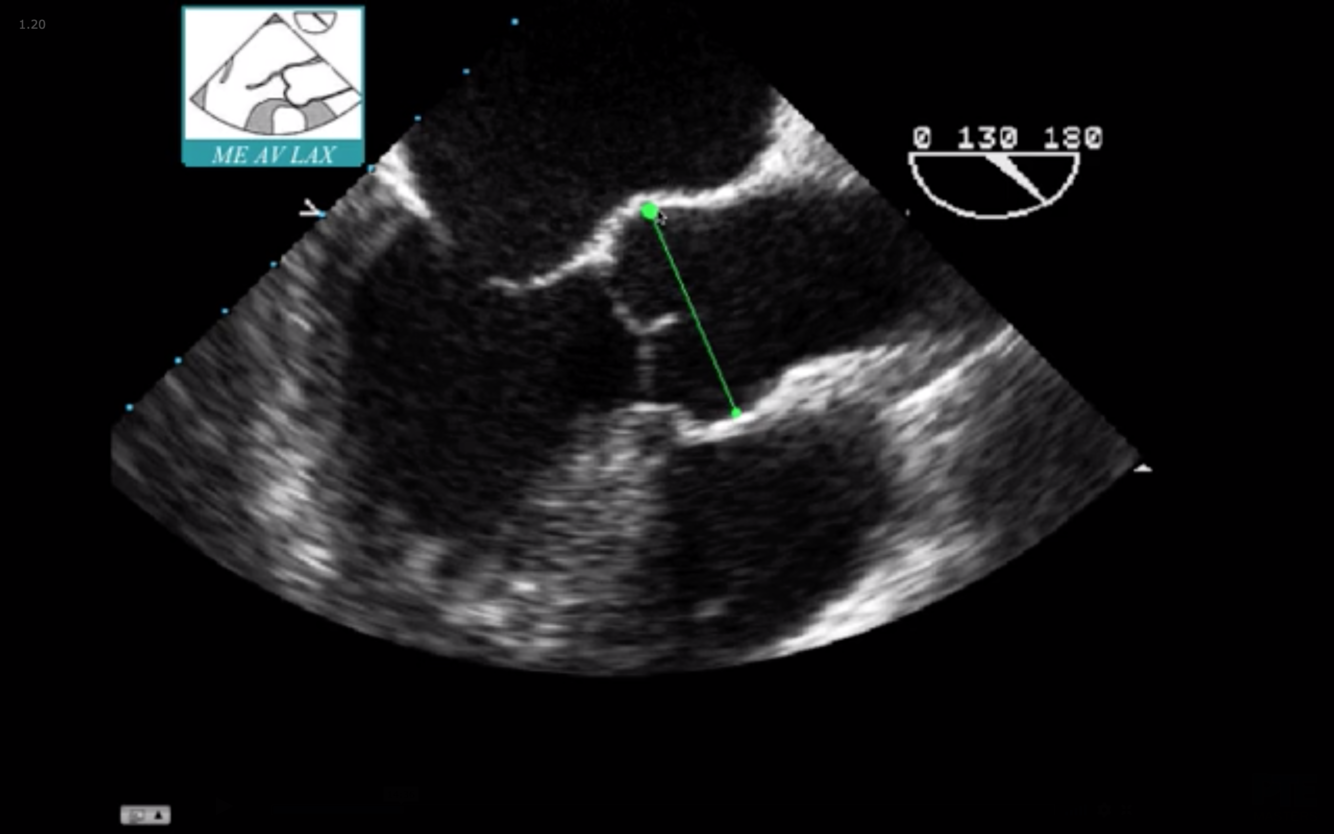

Find the ME AV LAX (120°)

Withdraw the probe to bring the right pulmonary artery in view

Decrease omniplane angle slightly by 10-20° to make the aortic wall symmetric